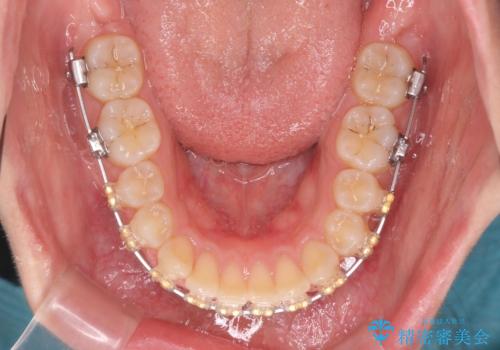

- 矯正装置

- ワイヤー矯正

ワイヤーを用いたマルチブラケット矯正を行うことで深い噛み合わせを改善し、前歯の隙間もなくし審美的な歯列へと治療をおこなっていきます。

深い噛み合わせの改善は前歯の圧下が必要なため、治療期間が長期化することが多いです。